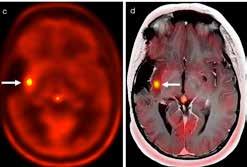

Led by Paul Northcott, PhD, Department of Developmental Neurobiology, researchers tracked the origin of Group 3 and Group 4 medulloblastoma to the rhombic lip, a structure present during early cerebellum development. Their findings were published in Nature. This is the first identification of a specific origin for Group 3

17

Magnetic resonance images of Group 3 and Group 4 medulloblastoma

medulloblastoma and reinforces prior findings about Group 4.

Northcott’s team leveraged the first-ever atlas of human cerebellar development to look for transcriptomic signatures of

medulloblastoma subgroups. In addition to implicating the rhombic lip in Group 3 and Group 4 origins, they found that cells differentially branch off from this shared path, explaining why Group 3 and Group 4 tumors have both overlapping and unique characteristics.

“We’ve had evidence that these groups had some kind of common ancestry that then likely diverged, depending on the genetic events driving those tumors, but we couldn’t say that definitively until now,” said Northcott.